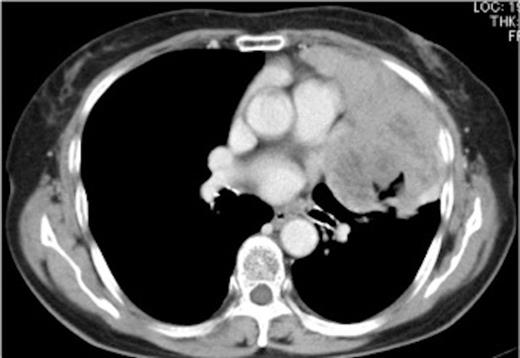

An 81-year-old woman was admitted to our hospital for examination and treatment of an abnormal shadow seen on chest radiograph. She had no symptoms on admission. Tumor markers were within the normal range. Acetylcholine receptor antibody (ARA) was negative. Her lung function was normal. Chest computed tomography (CT) showed a bulky mediastinal tumor bulging outward into the left thoracic space (Figure 1).

Preoperative chest computed tomography (CT) showing a bulky mediastinal tumor bulging outward into the left thoracic space and invading the pericardium and pleura.